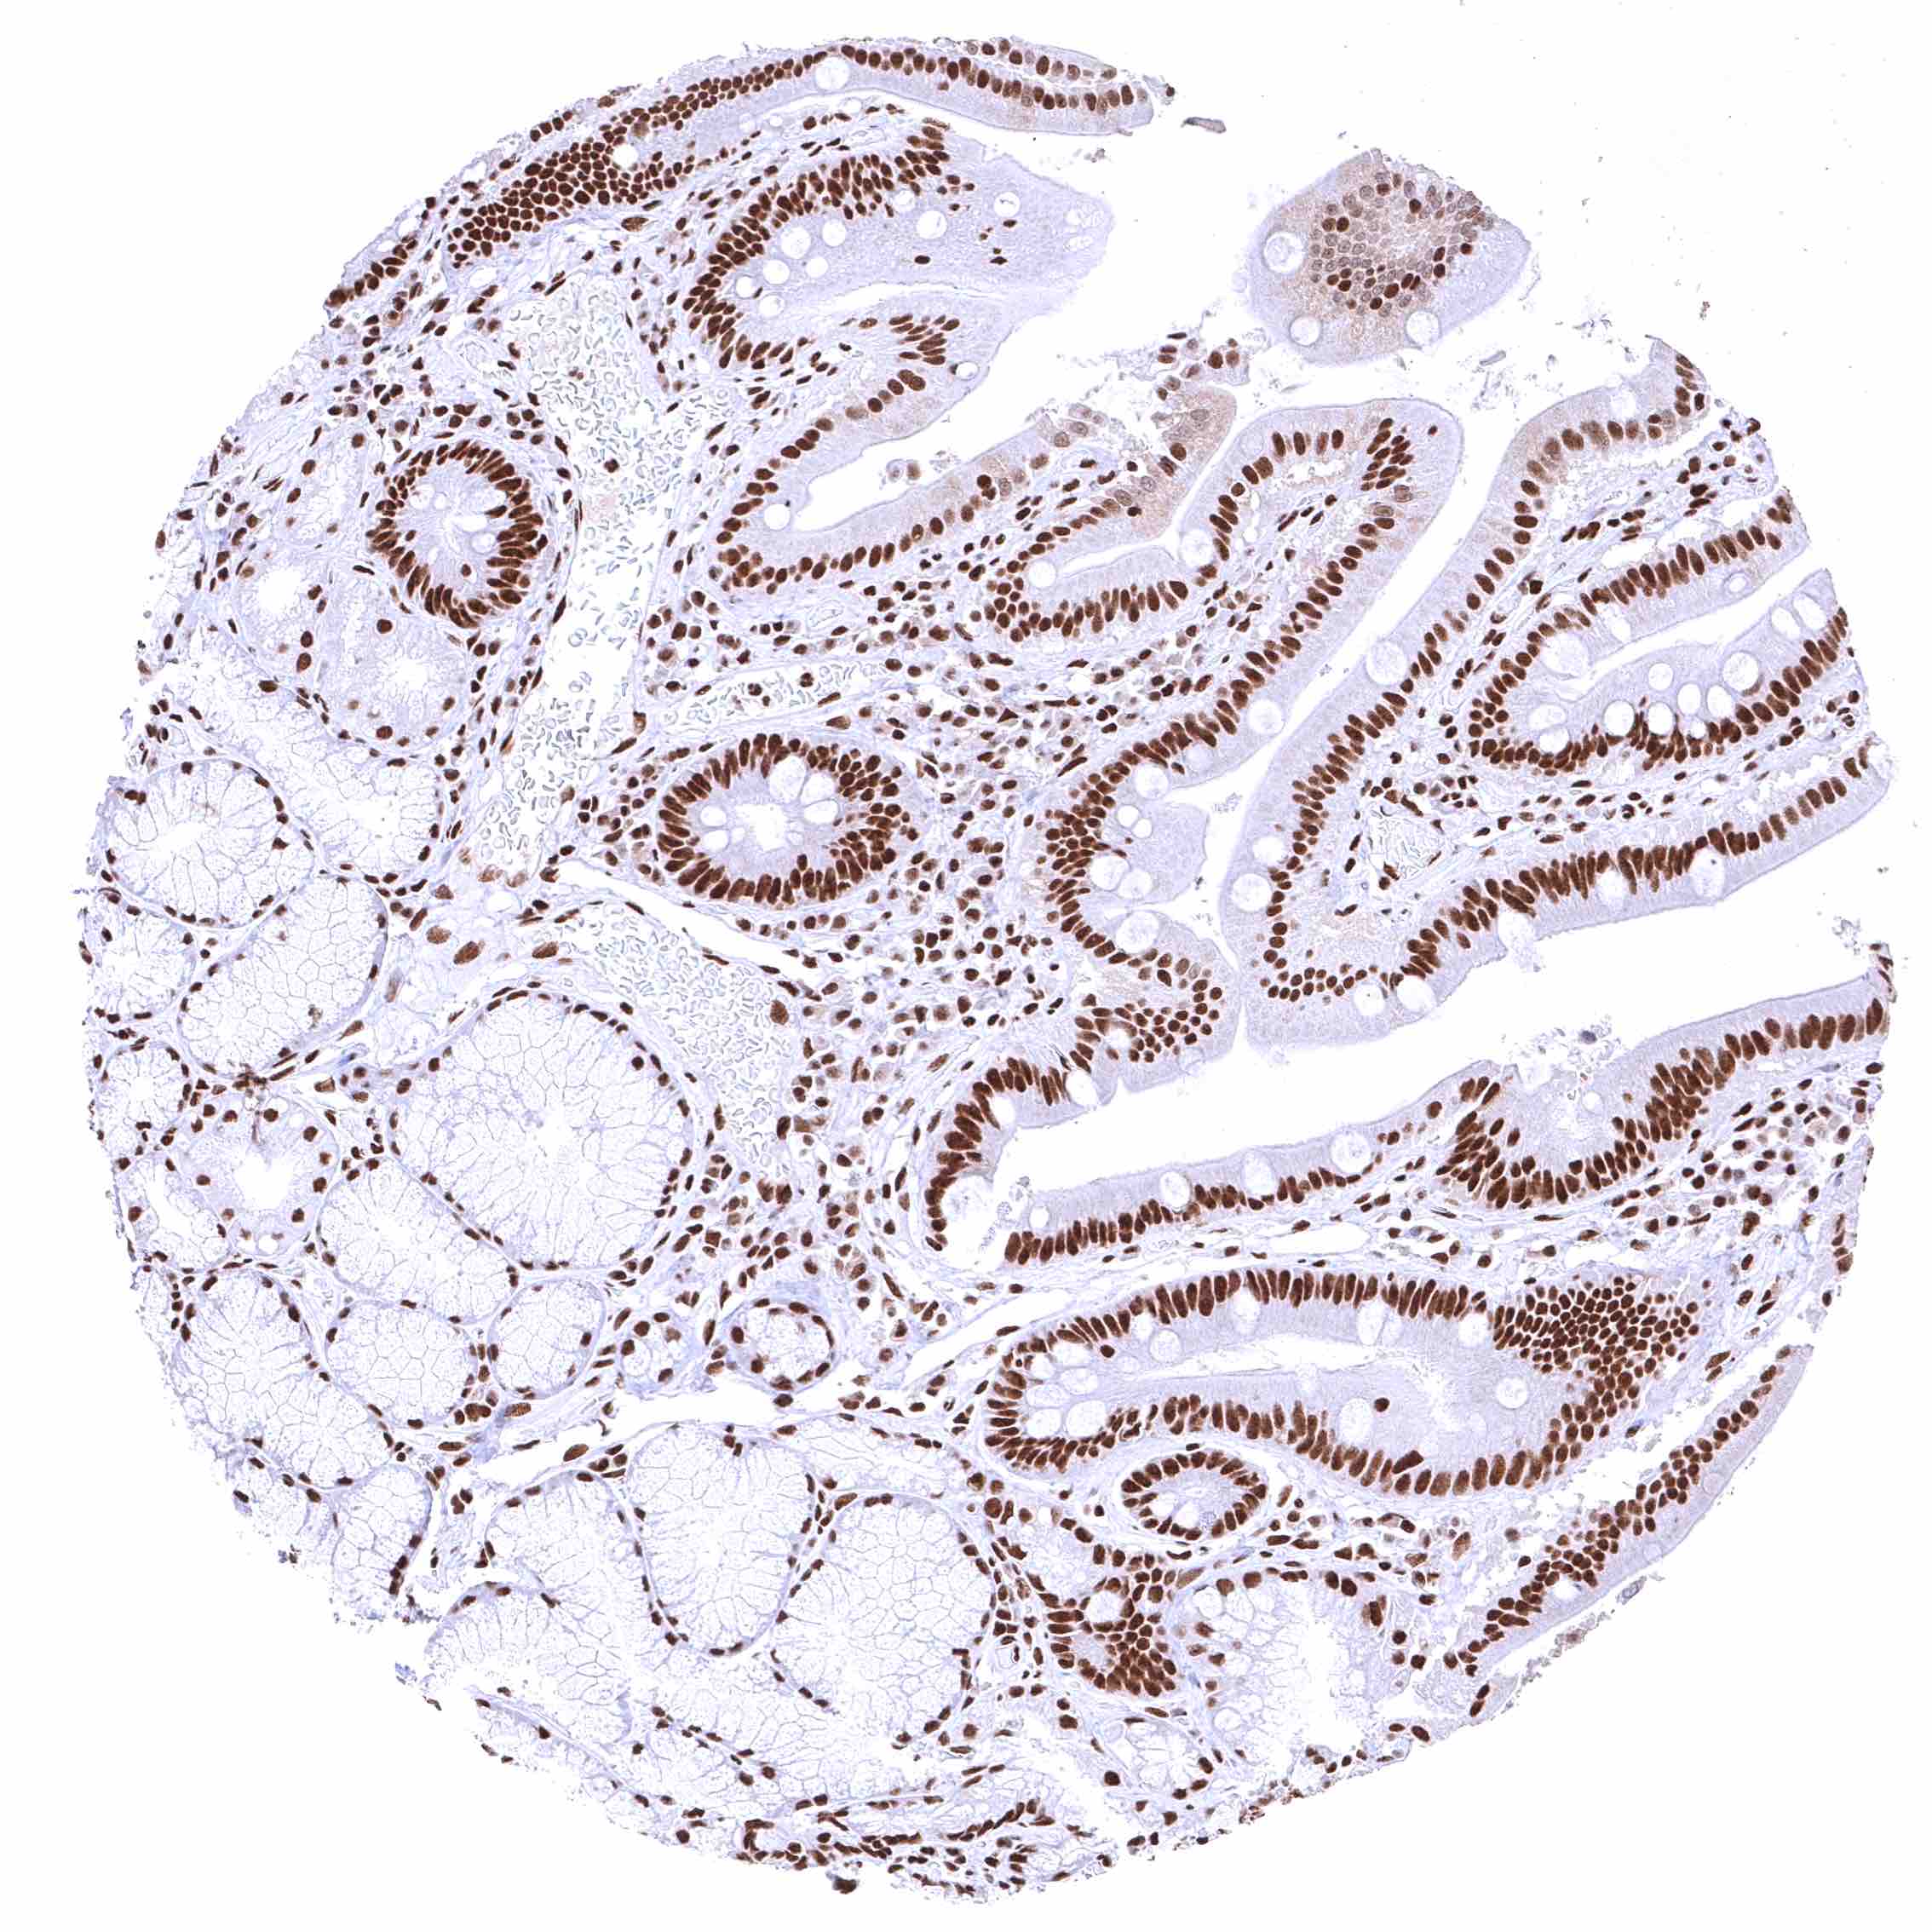

Colon descendens, mucosa – Nuclear BRD4 staining of surface epithelial cells is weaker than in crypts.